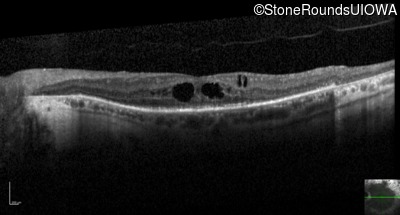

Optical Coherence Tomography - Right - 20/50 -1

Exemplar / OCT Stack

OCT Stack